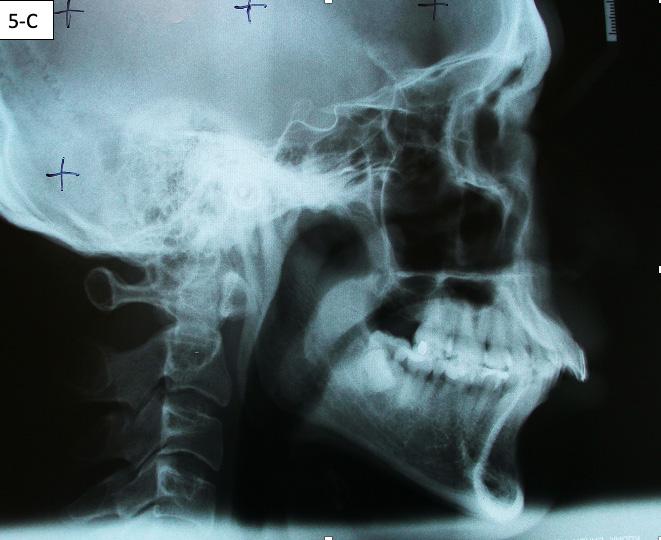

Lateral Cephalometric radiogram and tracing revealed robust lower airway (18.0/15mm), CVMS 6, maxilla and mandible are prognathic (SNA - 93° and SNB - 84°), Class II skeletal (ANB –9.0 mm, Witts – 9.0 mm). The patient was hyperdivergent (NS/ GoM – 30°, ALFH - 83 mm!!), protrusive maxillary incisors (U1/ SN – 117.0°), mandibular incisors were within the norm (L1/GoM 95.0°) and Harvold Δ was 30 mm. The soft tissue profile (lips) was convex (Figure 5-C, D).

FIG. 5C: Pre-treatment, Cephalometric radiogram